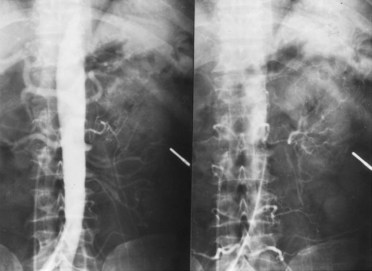

Angiography in primary intimal fibroplasia reveals a smooth, fairly focal stenosis, usually involving the proximal or midportion of the vessel or its branches (Fig. 39–3). Dissecting hematomas may distort the area of the stenosis. With nonoperative management, progressive renal artery obstruction and ischemic atrophy of the involved kidney invariably occur. Severe intimal fibroplasia may subsequently develop de novo in the contralateral renal artery. Although primary intimal fibroplasia most commonly affects the renal arteries, it may also occur as a generalized disorder with concomitant involvement of carotid, upper and lower extremity, and mesenteric vessels.

Figure 39–4 Selective right renal arteriogram reveals medial fibroplasia involving the main renal artery with typical “string of beads” appearance.

(From Novick AC. Renal vascular hypertension in children. In: Kelalis PP, King LR, Belman AB, editors. Clinical pediatric urology. Philadelphia: WB Saunders; 1984.)